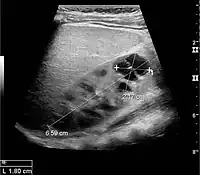

Figure 5. Simple renal cyst with posterior enhancement in an adult kidney. Measurement of kidney length on the US image is illustrated by '+' and a dashed line.[1]

Figure 6. Complex cyst with thickened walls and membranes in the lower pole of an adult kidney. Measurements of kidney length and the complex cyst on the US image are illustrated by '+' and dashed lines.[1]